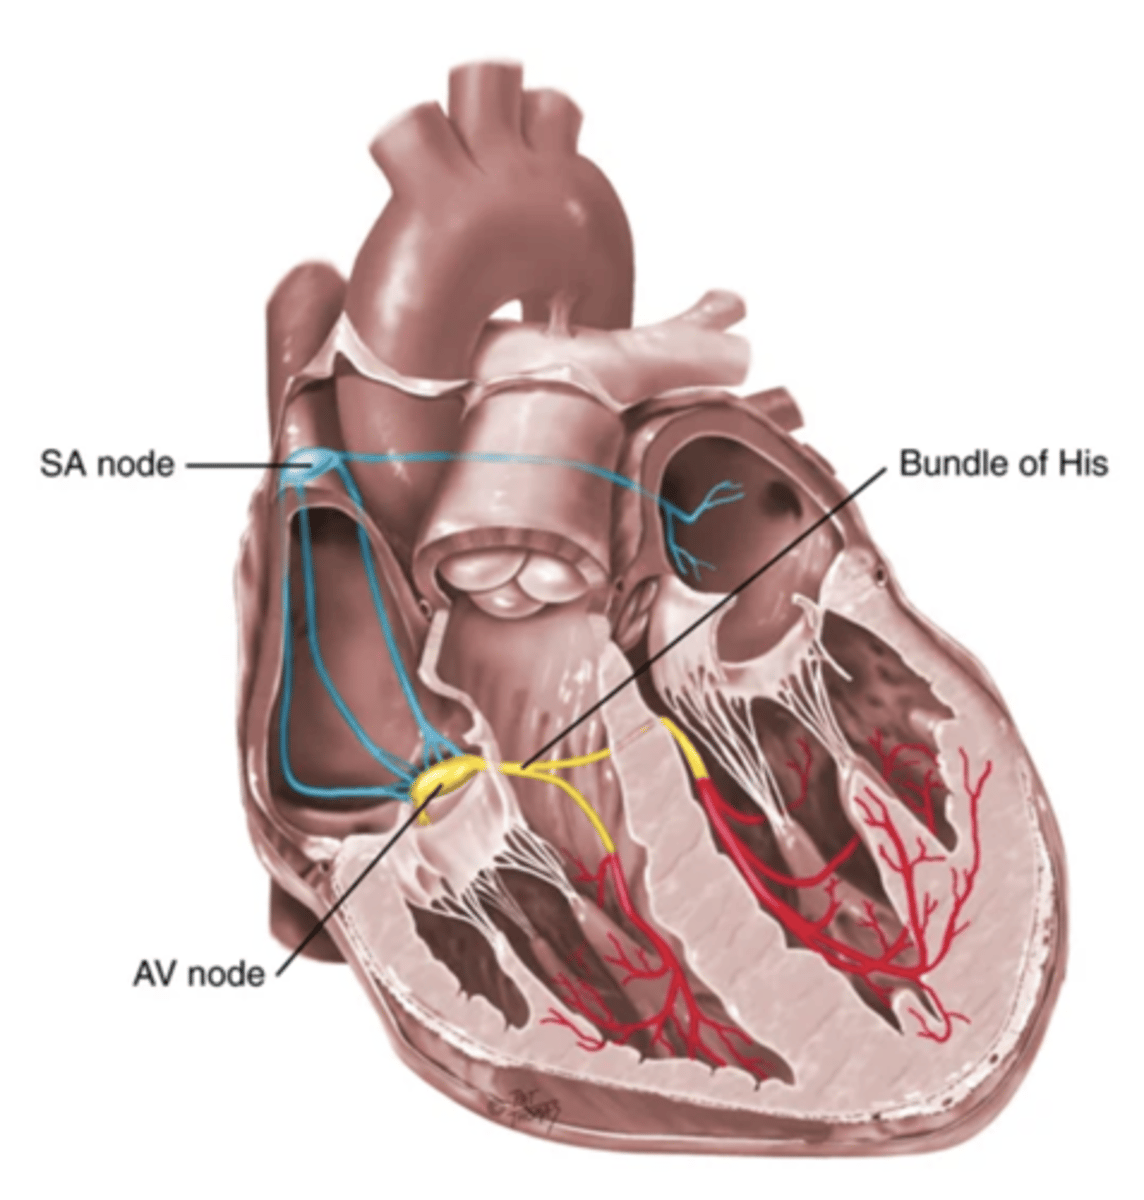

4 Parts of the Heart's Conduction System

- Sinoatrial (SA) node

- Atrioventricular (AV) node

- Bundle of His

- Purkinje fibers

Sinoatrial (SA) Node

Pacemaker of the heart conduction system, located at the right atrium (light blue)

Atrioventricular (AV) Node

The part that relays electrical impulses from atria into the bundle of his in the heart's conduction system; delayed slightly (yellow)

Bundle of His

Part of the heart's conduction system that transmits the cardiac impulse from the atrioventricular node to the purkinje fibers (red)

Purkinje Fibers

Fibers in the ventricles that transmit impulses to the right and left ventricles, causing them to contract